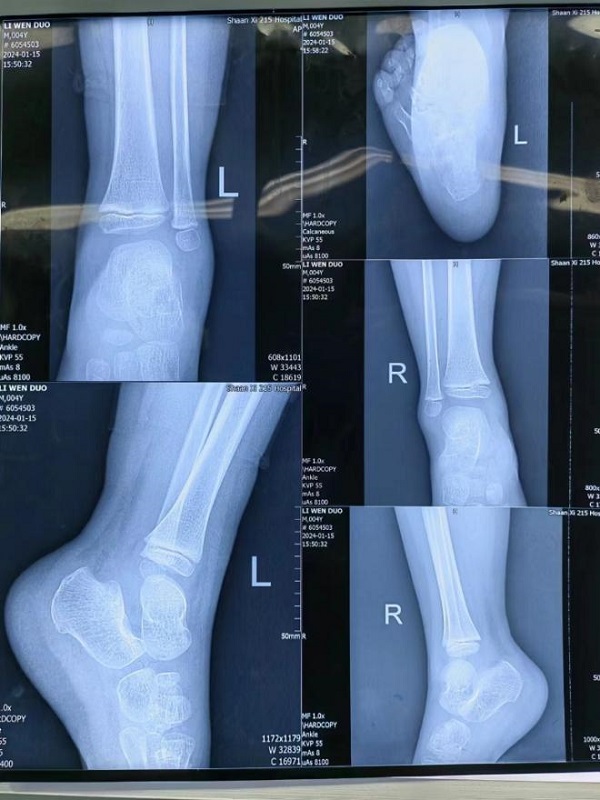

在二一五医院入院时,小铎的左脚红肿异常,一落地就疼痛难忍。足踝外科宋强主任迅速为小铎查体,完善相关基础检查,并根据检查结果诊断小铎为左脚跟骨骨折。

病情研判过程中,考虑到孩子年龄尚小,必须以最小的创伤完成治疗,用最快的速度让孩子恢复。宋强主任多频次组织团队阅片讨论,探究最佳诊疗方案。讨论认为,此例跟骨骨折涉及关节面,并且出现关节面塌陷,手术指征非常明确。在与家属充分沟通取得信任和支持后,宋强主任团队决定为小铎施行踝关节镜下微创手术治疗。考虑到儿童的病情进展较快,伤后第3天,手术便紧急开展。

手术过程中,关节镜从微小的窗口进入患儿体内探查,将病灶部位情形以最大视角、最佳角度呈现在监视画面中。关节镜直视下发现,关节面分离移位的程度远超影像资料提供的片面数据,手术的难度与复杂程度比预想的要大很多。在关节镜的辅助下,宋强主任团队专注谨慎,每一个步骤、每一次下刀都力争分毫无差,凭借多年累积的专业经验和技术水平,在约一个半小时的精细操作后,关节成功复位,手术精准且顺利的完成。